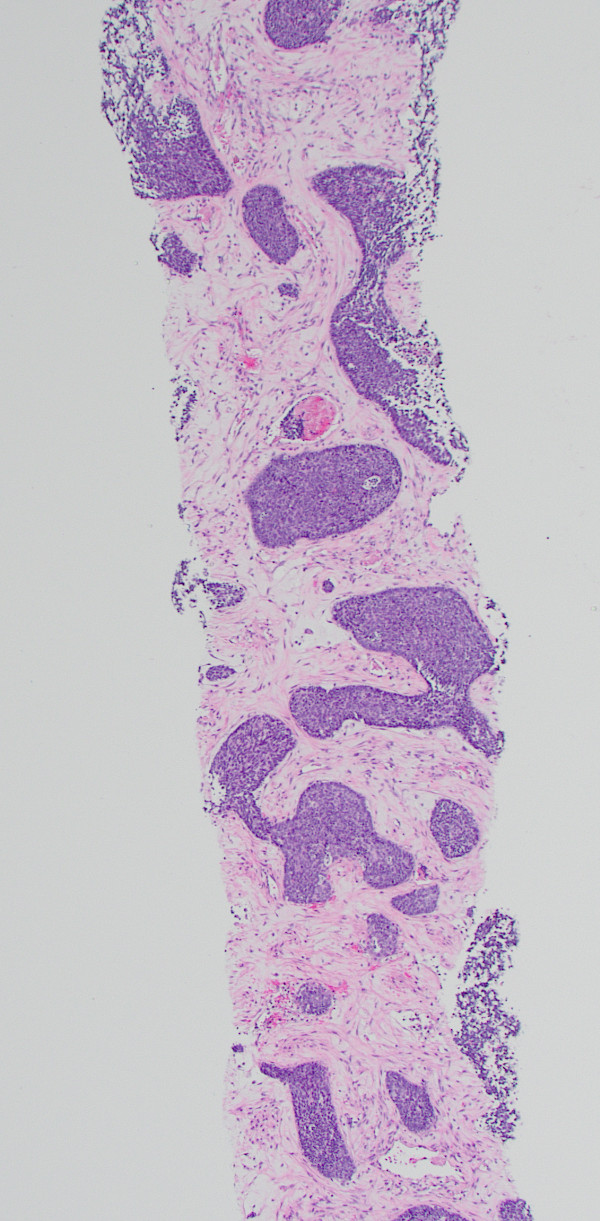

A liver biopsy was performed. H&E-stained sections of the liver biopsy demonstrated nests of malignant cells with scant cytoplasm and hyperchromatic, round nuclei. Numerous apoptotic bodies were seen (Figures 1, 2, and 3). Immunohistochemical stains were performed and the neoplastic cells were positive for cytokeratin AE1/AE3 (Figure 4), CD99, p16 (Figure 5), and INSM1 (focally positive). The neoplastic cells were negative for synaptophysin, chromogranin, and p40. High-risk human papillomavirus (HPV) in situ hybridization stain was positive. The Ki-67 labeling index was over 90% of the neoplastic cells. A concurrent biopsy of the uterine cervix was performed and had similar morphology to the liver lesion.